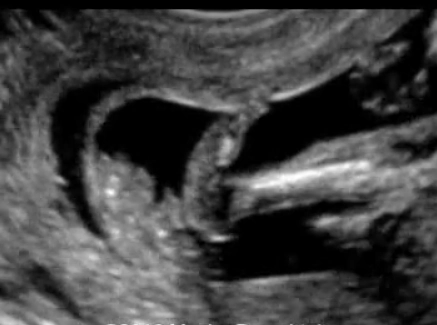

Bàn chân khoèo ở thai nhi (Clubfoot)